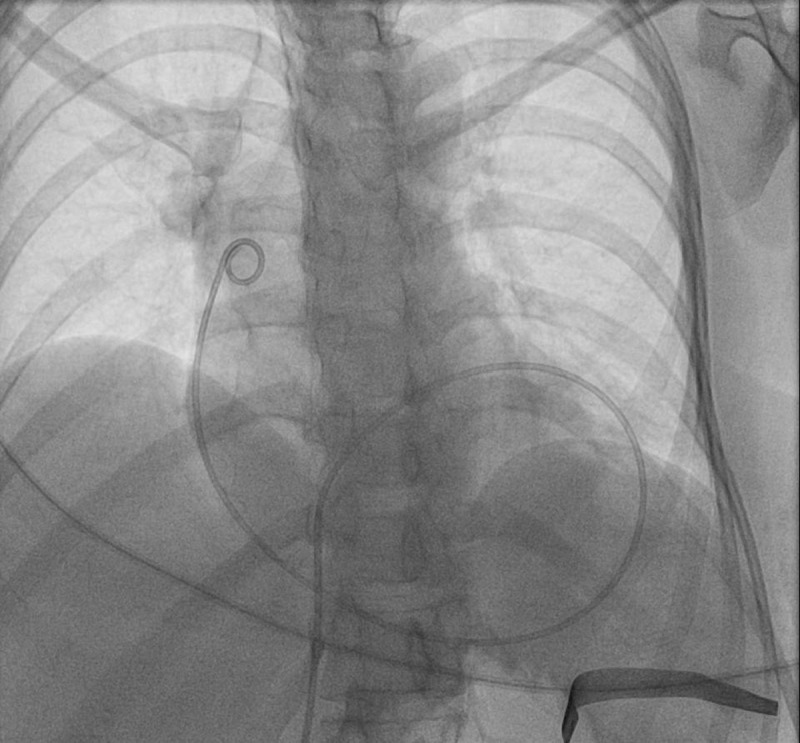

Chylopericardium (CP), defined as the accumulation of chyle in the pericardial cavity, is a rare condition, especially in the absence of an identifiable secondary cause. Primary idiopathic chylopericardium (PIC) is even more uncommon, with limited cases reported in the literature. We report the case of a 43-year-old South Asian woman who presented with palpitations and fatigue. Echocardiography revealed a large pericardial effusion with signs of cardiac tamponade, necessitating emergent pericardiocentesis. The pericardial fluid aspirated was pinkish and turbid, which turned to milky white after centrifugation. Analysis of the pericardial fluid demonstrated a high triglyceride concentration, lymphocytic predominance, and fat globules, consistent with chylous effusion. A thorough diagnostic workup-including infectious, rheumatologic, and oncologic evaluations-was unrevealing, confirming a diagnosis of PIC. Lymphoscintigraphy was misleading in this case, with no thoracic duct abnormalities reported. Following an initial response to conservative management with pericardiocentesis and a medium-chain triglyceride-rich diet, the patient experienced recurrence of symptoms and fluid reaccumulation. Definitive management via thoracic duct ligation and pericardial window surgery was performed, resulting in complete resolution of the effusion. At 6-month follow-up, the patient remained asymptomatic with no evidence of recurrence. This case highlights the importance of considering primary CP in the differential diagnosis of pericardial effusion. Absence of classical inflammatory signs and symptoms can be suggestive of chylous effusion. The report also supports surgical intervention as a definitive treatment even if lymphoscintigraphy does not reveal clear thoracic duct pathology.